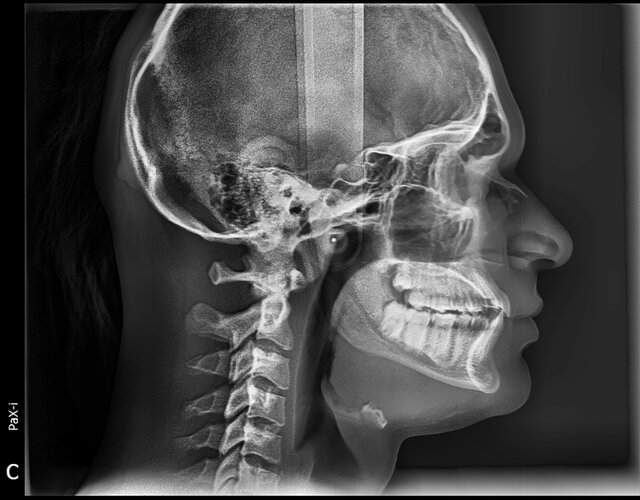

They want me to get elastic braces and see what we do maybe move with invisalign or whatever is best needed for my treatment. If you have decent knowledge in this field respond and give advice for treatment. pls don’t message if u don’t know anything low iq type move

If they are moving my jaw back I would know and not continue with him he wanted to do extractions but I told him I wanted to avoid recession so we are doing regular braces.